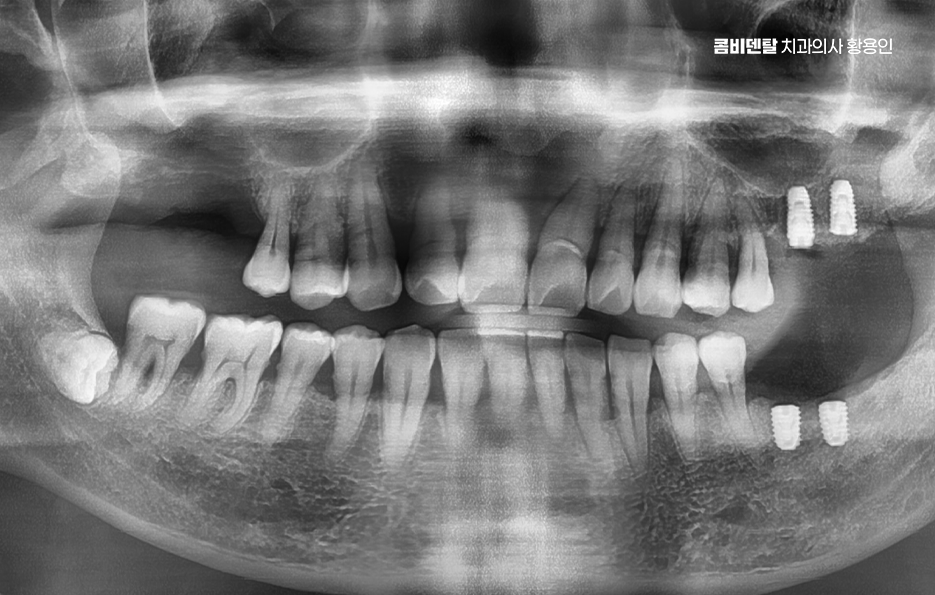

노년기에 자연치아를 잃게 되는 가장 흔한 원인은 치주질환으로 특히 60대 이후부터는 장기간 관리되지 않은 치주염이 진행돼서 결국 치아가 흔들리거나 빠지게 되는 경우가 많으며 일부는 오래된 보철물이나 충치가 원인이 되기도 하는데 자연치아가 하나 빠지면 단순히 그 부위만의 문제가 아니며 주변 치아들이 그 공간으로 쓰러지거나 이동하게 되고, 전체 치열이 무너지기 시작하는 거예요

그러면 한두 개의 상실이 전체 구강 구조를 무너지게 만들고, 결국은 씹는 힘도 약해지며 고령일수록 이런 변화가 더 빠르게 진행되기 때문에, 빠른 대응이 중요할 수 있었어요